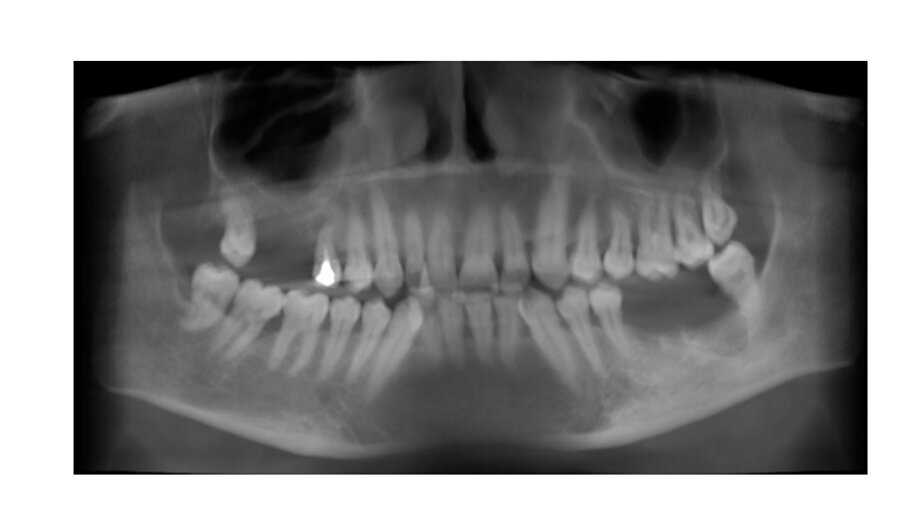

Una paziente donna di 63 anni, con osteoporosi ed ipotiroidismo, si presenta con assenza del 16 e 17, richiedendo riabilitazione dentale fissa. Si procede con l’esecuzione della CBCT per avere dettagli maggiori. Dall’analisi della CBCT nell’area edentula si misura un’altezza ossea verticale <5 mm in zona 16-17 e si nota la presenza di una lesione periapicale dell’elemento dentale 15 (Figg. 1-3). Quindi si programma l’intervento per l’estrazione del 15 e l’intervento per l’esecuzione del rialzo del seno mascellare con approccio laterale, con uso di osso bovino collagenato e spugnette di fibrina, al fine di ottenere l’incremento di osso verticale6. Dopo 5 mesi dall’esecuzione del rialzo di seno mascellare si esegue CBCT di controllo, per verificare l’effettivo aumento di osso verticale e programmare l’inserimento implantare (Figg. 4, 5).

A 5 mesi dall’intervento dal rialzo del seno mascellare con approccio laterale, grazie alla CBCT è stato possibile valutare la presenza di osso verticale. Si è visto che nell’area rigenerata si è avuto un incremento dell’osso, che presenta un range da 8 a 12 mm circa. Quindi verificata una rigenerazione verticale è possibile una riabilitazione implantare della zona 16, 17 e 15 con la scelta di impianti di lunghezza e un diametro adeguato (Figg. 4, 5)7, 8.